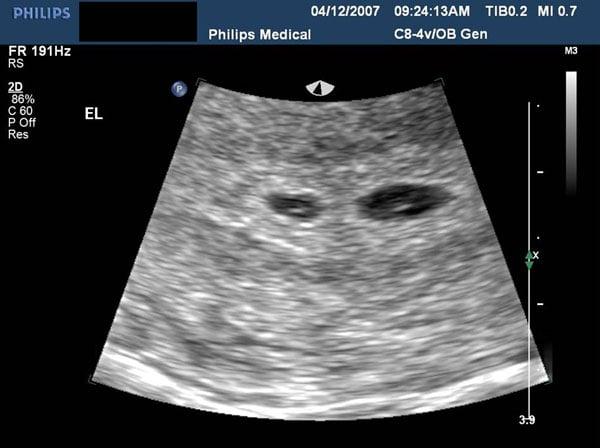

Master the critical role of sonography in diagnosing and managing Twin-to-Twin Transfusion Syndrome (TTTS) in monochorionic twins. This course covers the early detection and advanced sonographic findings of TTTS, including discrepancies in nuchal translucency, amniotic fluid volumes, and placental cord insertions. Learn the importance of early diagnosis through first trimester markers, and explore the second and third trimester findings such as growth discordancy, polyhydramnios, and abnormal Doppler waveforms. Gain expertise in using Quintero staging to assess the severity of TTTS and understand how treatments like amniocentesis and laser surgery can improve outcomes. The course also discusses long-term outcomes for both donor and recipient twins after TTTS interventions, including cardiovascular adaptation and neurodevelopmental implications. This course is designed for clinicians seeking to improve the survival rates and management strategies for TTTS in twin pregnancies.

describe the sonographic findings with twin-to-twin transfusion syndrome.